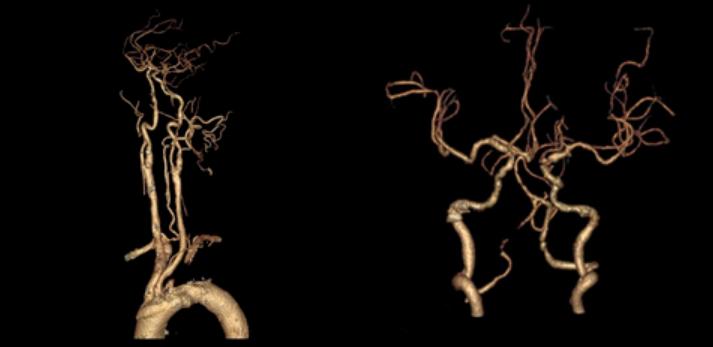

十九、锁骨下动脉盗血综合征合并开窗畸形

例37:左锁骨下动脉起始段闭塞、左侧锁骨下动脉盗血综合征合并基底动脉近段开窗畸形